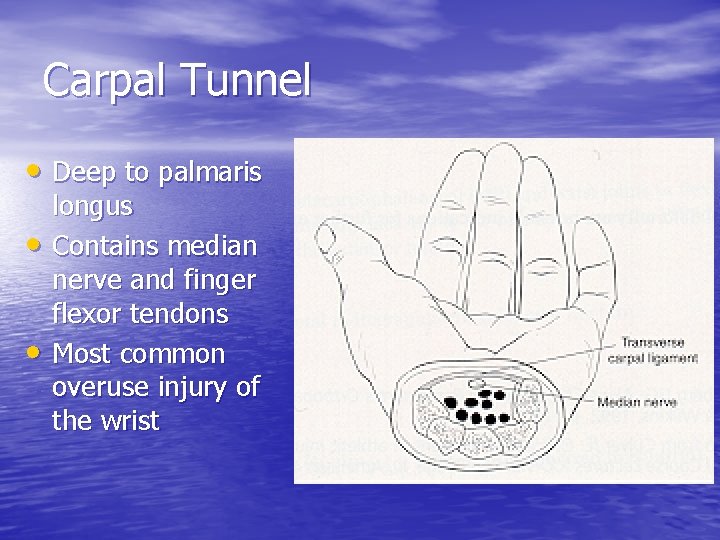

Carpal Tunnel • Deep to palmaris • • longus Contains median nerve and finger flexor tendons Most common overuse injury of the wrist